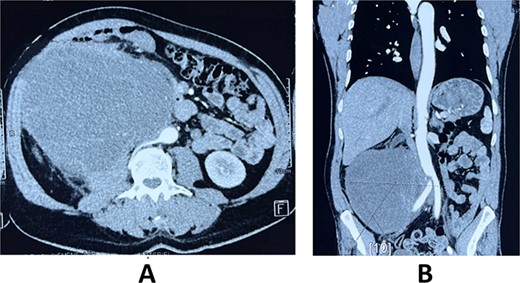

A 59-year-old male patient, known to have hypertension controlled by medication with no previous abdominal surgeries or any remarkable family history, presented with the complaint of a palpable indolent abdominal mass and vague abdominal fullness evolving for 4 months. The patient denied gross hematuria and lumbar pain. Clinical examination showed, on inspection, a visible large abdominal mass occupying the right hemiabdomen. The mass was hard and fixed to deeper layers. Neither jaundice nor dilated skin veins was found. Lab tests were normal. A thoraco-abdominal-pelvic computed tomography with contrast medium and delayed phases was performed. It showed a large right retroperitoneal solid mass measuring 190 × 140 × 120 mm with a thickened lobulated wall. It was heterogeneously enhancing, managing hypoattenuating areas, compatible with necrosis. It was responsible for anterior displacement of intestinal loops and pushed laterally the right colon. It crossed the midline displacing medially the inferior vena cava, abutting the abdominal aorta. Right mild hydronephrosis was found by direct invasion of the ureter. No clear dependence of any of the adjacent organ was identified. No metastatic lesions were found (Fig. 1).

Axial (A) and frontal (B) view of Computed tomography scan showing a large right retroperitoneal solid mass, with lobulated thickened wall measuring 190 × 140 × 120 mm, heterogeneously enhancing, displacing anteriorly duodenal loops, laterally the right colon, medially the inferior vena cava and abdominal aorta.